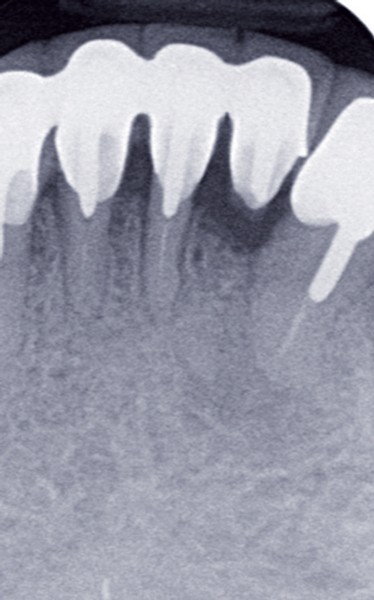

Le contrôle radiologique rétro-alvéolaire montre, quant à lui, une parfaite préservation de l’ostéointégration à 6 ans(fig. 3a et b).

Cette ostéointégration est confirmée par le Cone Beam(fig. 4a et b).